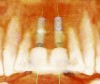

Fig 2. Cross-sectional view of proposed implant

position. Note that the plan allows the restorative doctors and surgeon to confirm the implants’ position, inclination, depth, and

emergence.

Figure 2

The DICOM (digital imaging and communications in medicine) images are then imported from the CBCT files into one of many commercially available implant-planning software programs. The surgeon and restorative dentist can then collaborate in choosing the precise position, angulation, and depth of implant placement, as well as the implant type, based upon a desired prosthetic outcome. Rosenfeld et al coined the term “collaborative accountability” to describe the pretreatment analysis and subsequent negotiated compromises between surgical and restorative colleagues on implant positioning and restorative design based upon anatomic limitations and the team’s willingness and ability to overcome them.3 Additionally, this pretreatment evaluation is invaluable in creating realistic patient expectations. Figure 1 through Figure 6 demonstrate a case showing 3-dimensional (3-D) presurgical planning, radiographic evidence of the plan’s execution, and 2-year follow-up. As a result of 3-D planning and subsequent guided implant surgery, the patient wound up with a pleasing, nature-like esthetic outcome (Figure 5).